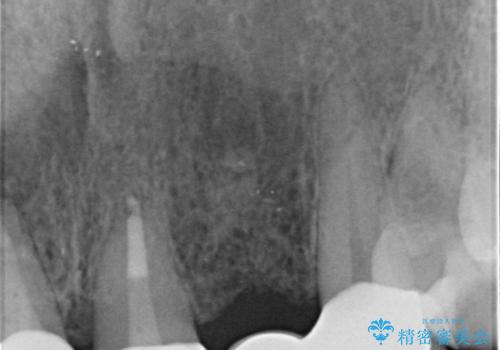

- 入れ歯での生活がストレスで他のものに変えたいとのことで来院された患者様です。

根の状態も良くなかったため、根管治療から行うこととなりました。

左上2番の歯は歯根が割れていたため抜歯し、入れ歯をブリッジに変えていきます。